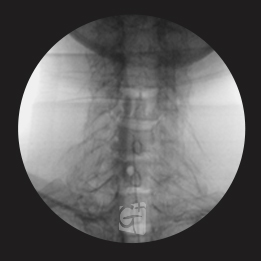

요추 경막외 신경치료

요추 4/5번 경막외 공간에 약물을 주입,

신경줄기로 잘 퍼지는 모습